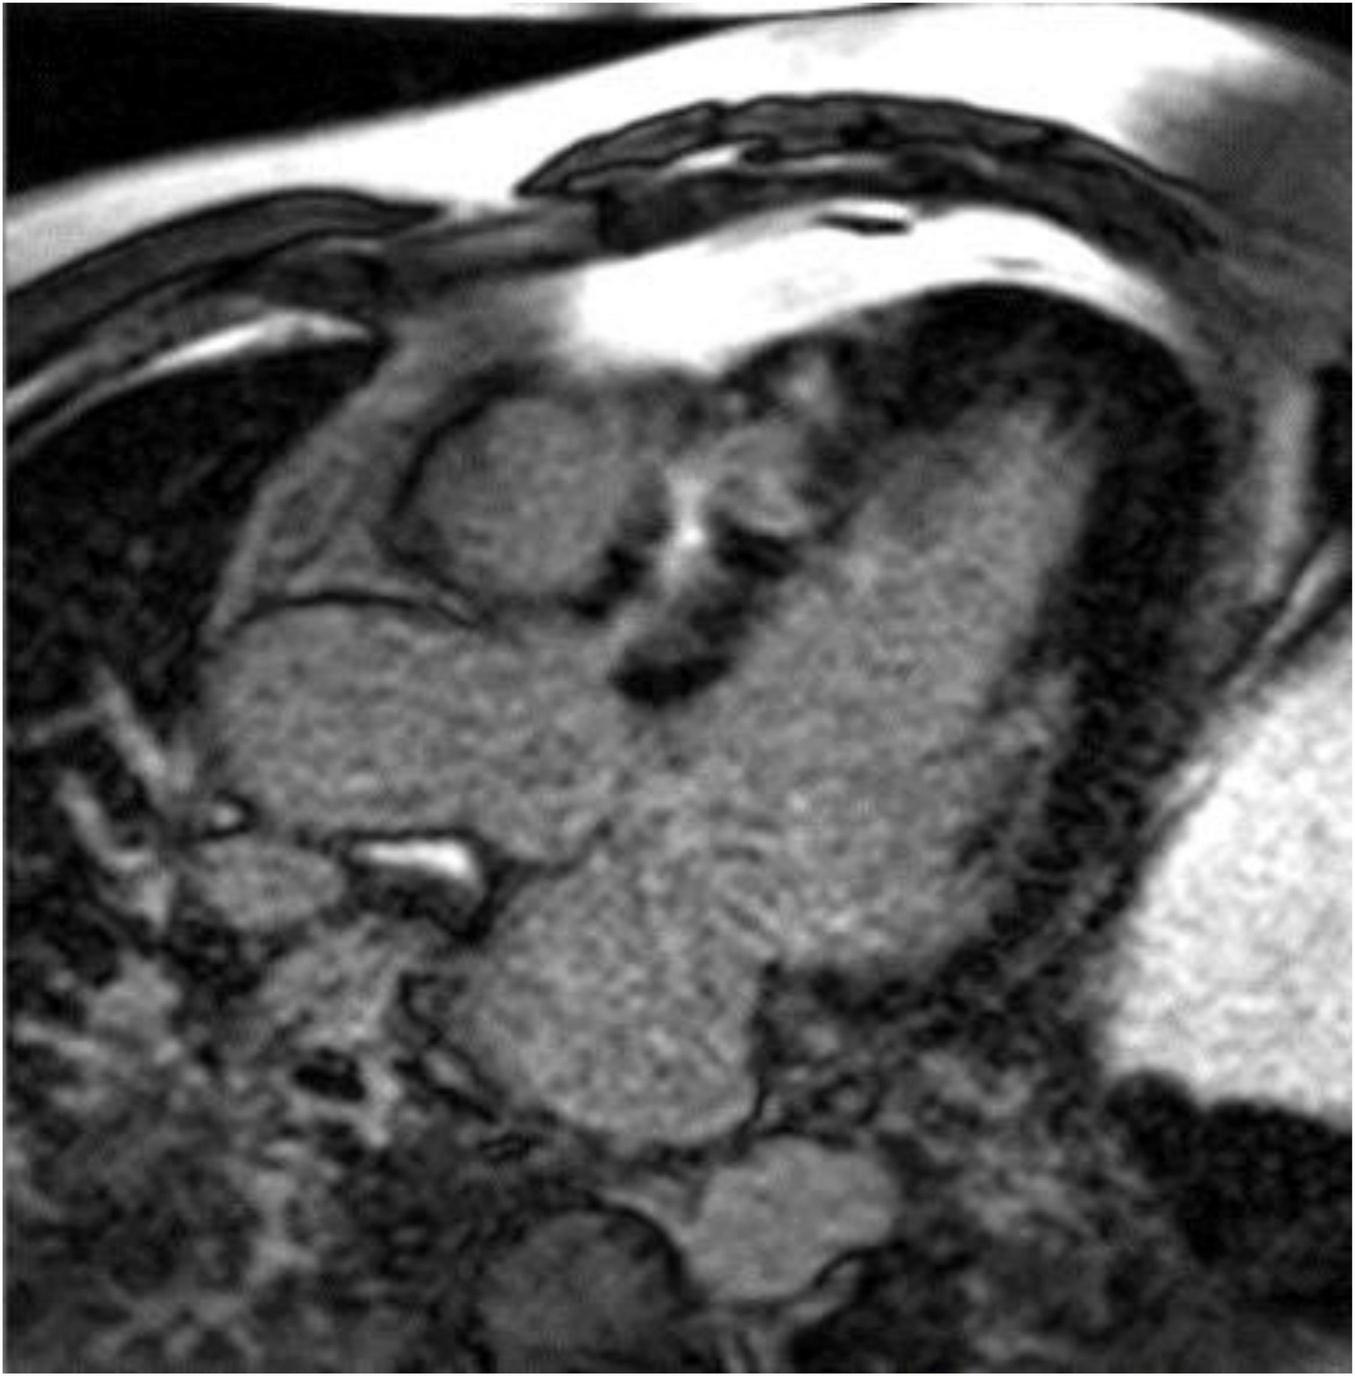

Cardiac MR is not specifically recommended by current HCM guidelines for pregnant women or women who may become pregnant. However, CMR does offer advantages over echocardiography, for example by visualizing maximal wall thickness, detection of apical aneurysms, and identification of late gadolinium enhancement (Figure 4) (55). Each of these features has been associated with adverse outcomes in the general HCM population and may plausibly be associated with higher risk during pregnancy. CT has limited recommendations in the guidelines and essentially is considered appropriate for patients who cannot undergo CMR but require imaging beyond echocardiography (56).

FIGURE 4

Late gadolinium enhancement (LGE) image from a cardiac magnetic resonance image in the three-chamber view showing significant fibrosis in the anteroseptum of a patient with hypertrophic cardiomyopathy. Image courtesy Arlene Sirajuddin, MD.